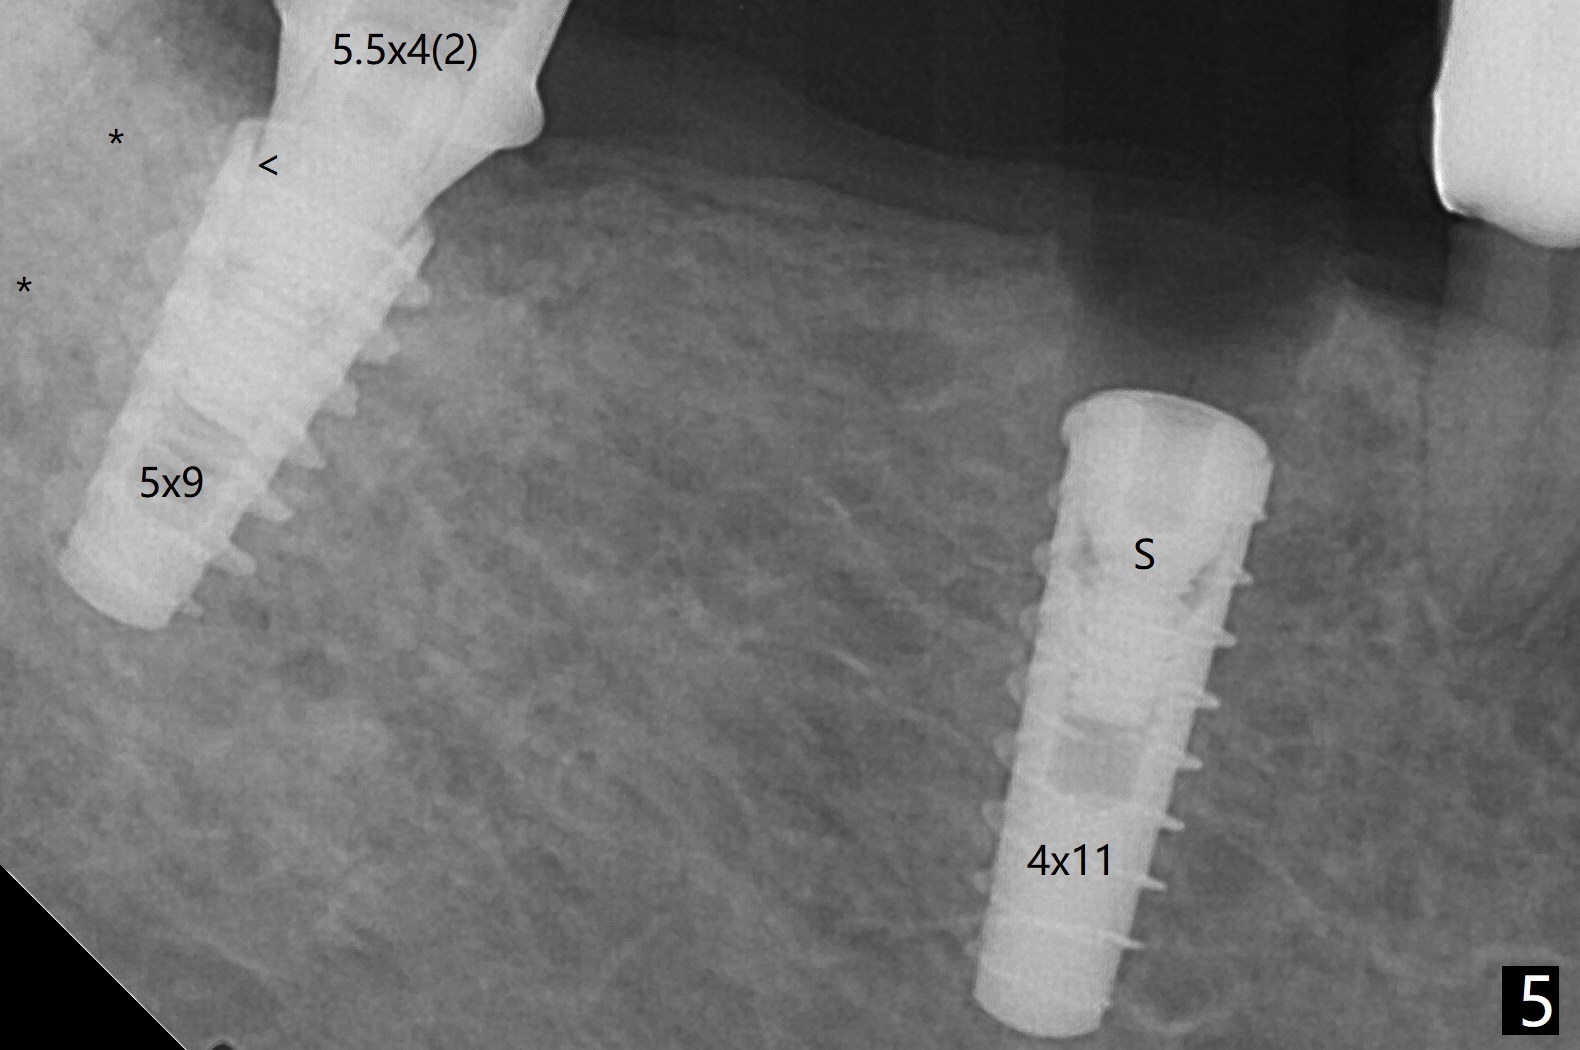

The keratinized gingiva at #29 is slightly lingual with torus mandibularis (Fig.1 *). 4 mm tissue punch through metal sleeve makes a superficial mark (Fig.4). To save the keratinized tissue, a lingual flap is designed as shown in Fig.4 insert (black line; avoiding the torus *). Osteotomy involving 4 mm cortical drill is related to <10 Ncm insertion torque of a 4x11 mm implant; a healing screw is placed (Fig.5 S). After removing the torus and placement of bone graft and collagen plug (Fig.6 *), the lingual flap is sutured in place without tension because of the torus resection (Fig.7 *). Later the wound is covered by periodontal dressing.

The extraction socket of #31 has a thin septum (Fig.2), which is removed partially with 12 mm bone trimmer (Fig.3). After placement of a 5x9 mm FC implant (~40 Ncm) and 6 mm bone profile drill, a 5.5x4(2) mm abutment is incompletely seated (Fig.5 <) and later is changed to a 4.5x1 mm temporary abutment (Fig.6, 8 T). The latter is used to fabricate a provisional, which in turn supports the distal papilla (Fig.8 *). The gingiva is slightly erythematous immediately post periodontal dressing removal (3 weeks postop, Fig.9). Take CT to confirm whether the cortical drill helps keep the #29 implant lingual. Use a profile drill at #29 if crestal bone loss is not obvious. There is bone coronal to #29 implant 4 months postop (Fig.10). Upon incision, the ridge is rounded (Fig.10'), but the implant appears to be buccally placed (Fig.10'' (post high speed handpiece and 5.5 mm profile drill)). The latter is confirmed by CT (Fig.12, as compared to design (Fig.11)). In spite of use of cortical drill coronally, the implant is still deviated buccally due to contrasting deferential bone density linguobuccally (Fig.13). By comparison, there is no such bone density differential involving an immediate implant at #31; the implant is placed in the socket without contacting the buccal or lingual cortices (Fig.14). The final implant is the same as expected (Fig.15). To avoid implant deviation in the lower premolar region, leave the root in place until osteotomy is finished. Five months postop, the temporary and healing abutments at #31 and 29 change to pair ones (Fig.16). Since there is limited clearance from the crestal bone, smaller abutments are used with the apparently same degree of seating (Fig.17). The abutments are prepared due to the mesial (#31) and buccal (29) tilt before impression.